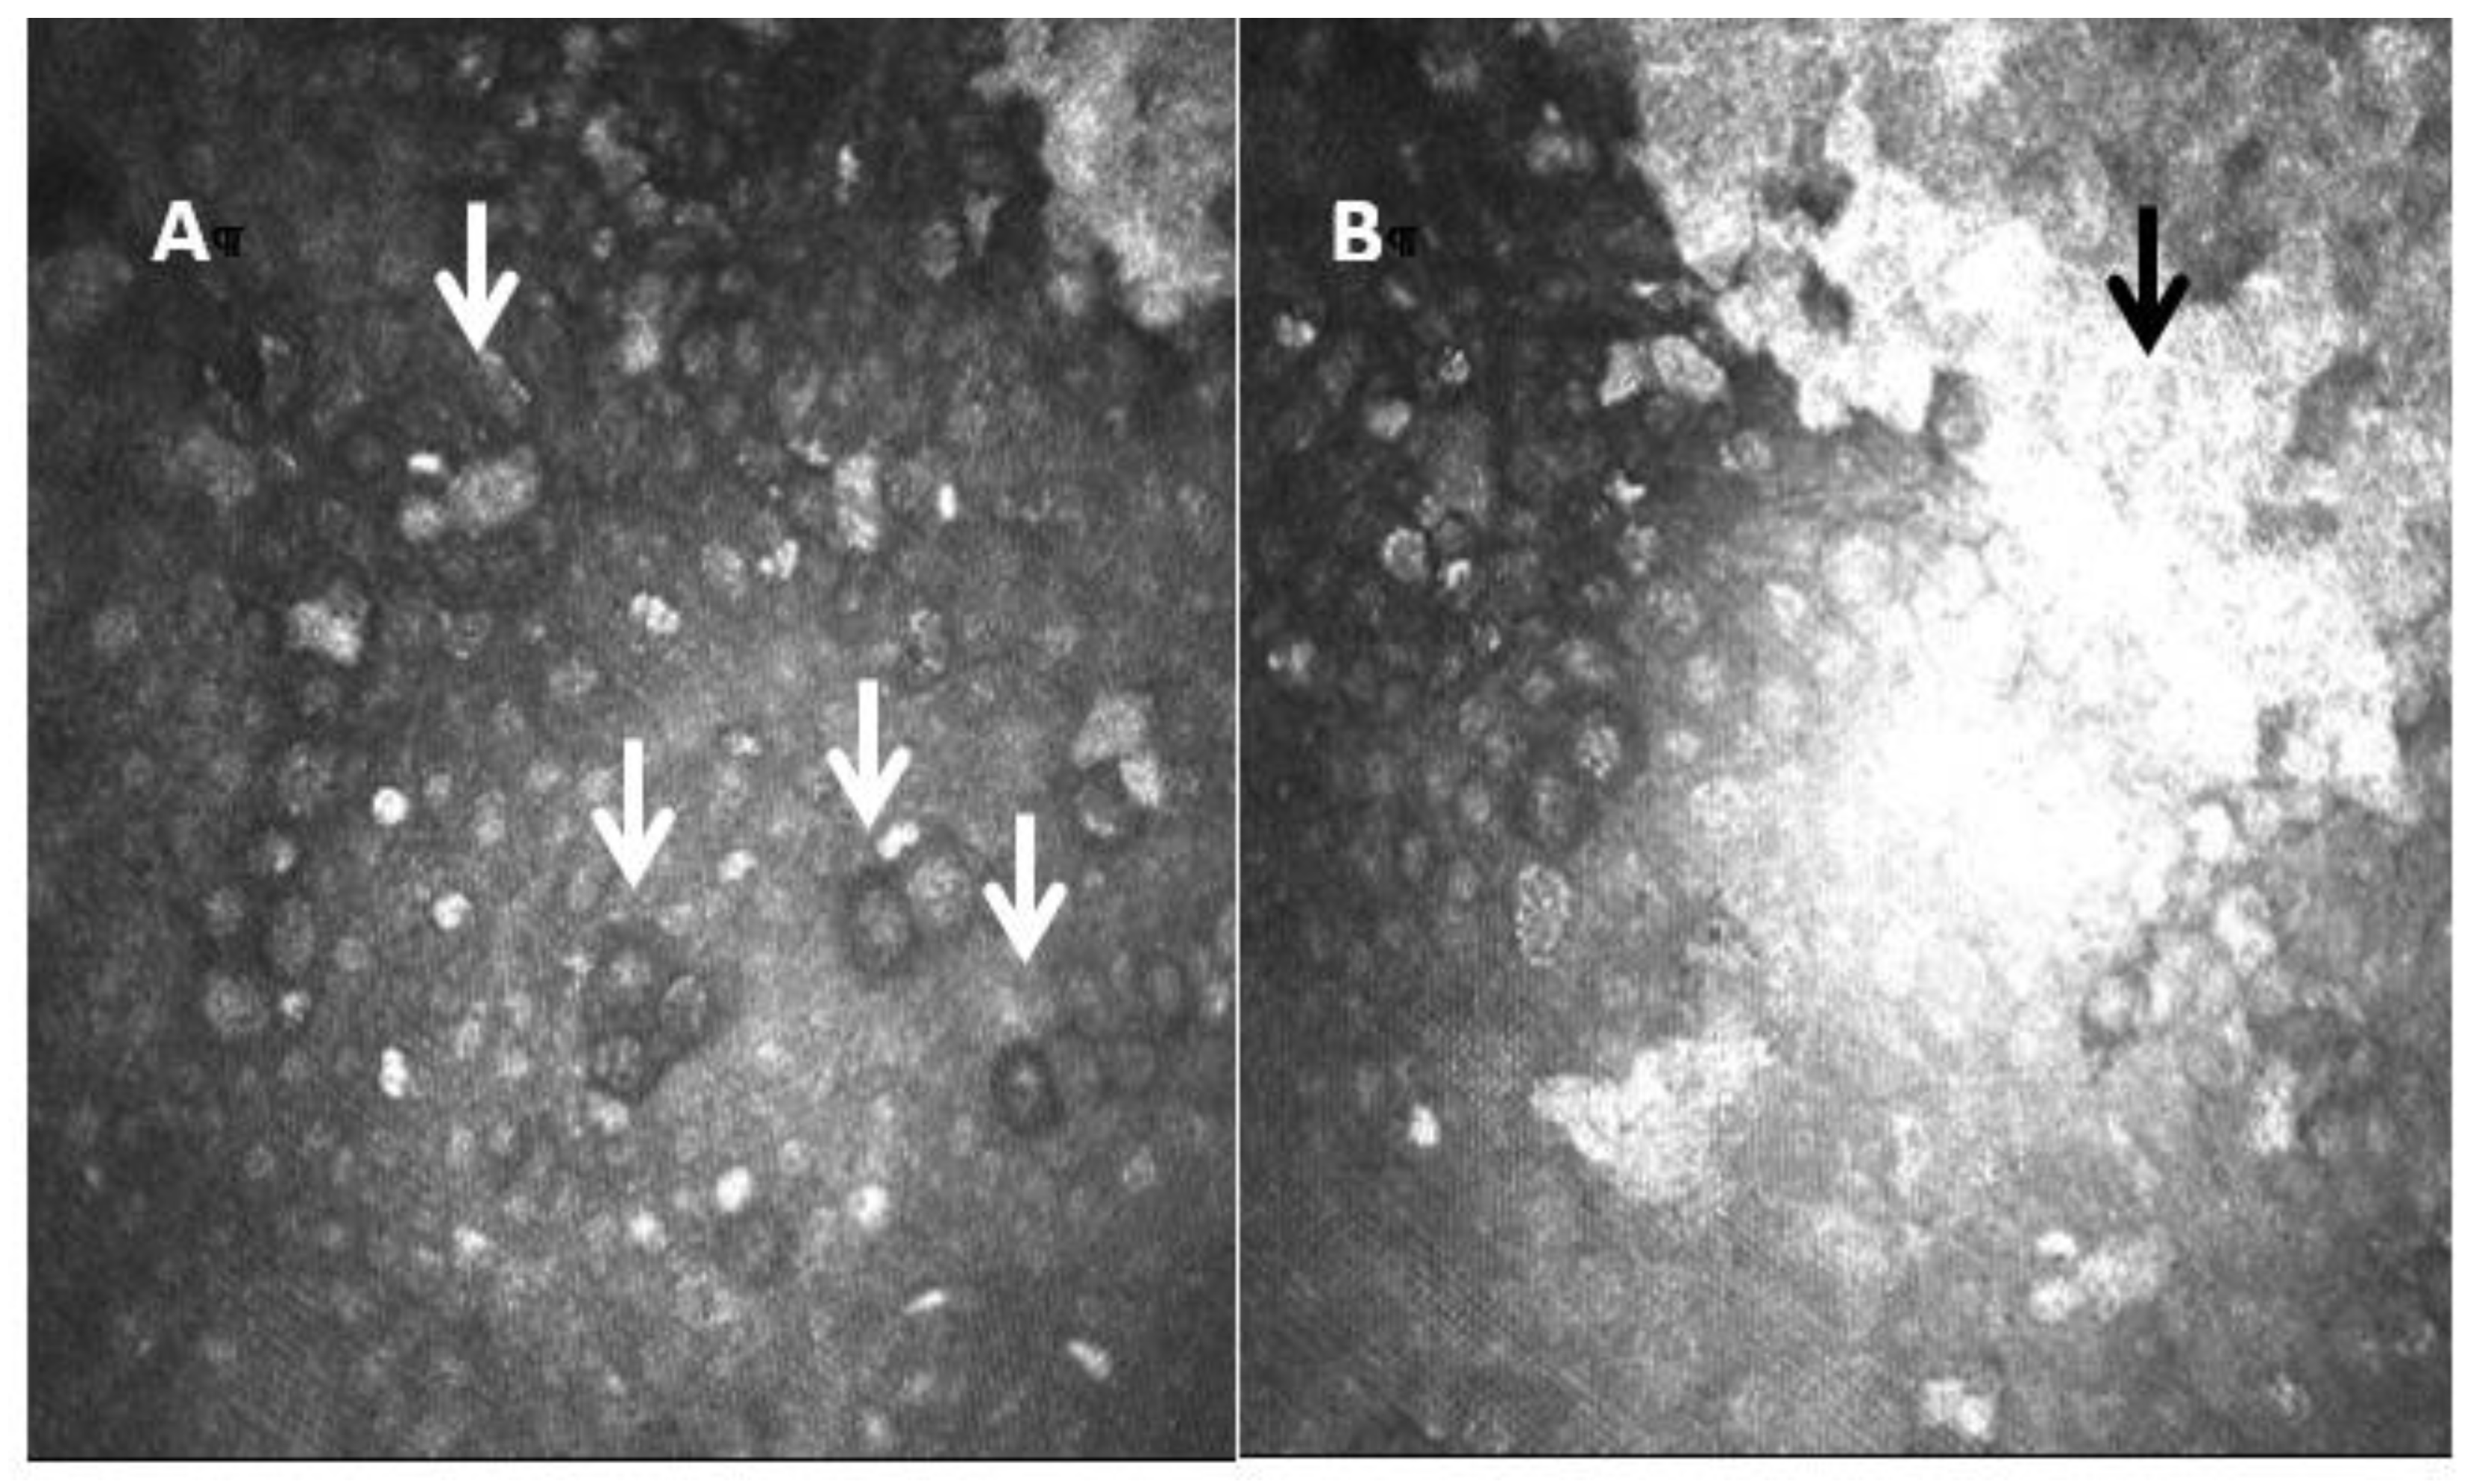

- Maycock, N.J.; Jayaswal, R. Update on Acanthamoeba Keratitis: Diagnosis, Treatment, and Outcomes. Cornea 2016, 35, 713–720. [Google Scholar] [CrossRef] [PubMed]

- Tu, E.Y.; Joslin, C.E.; Sugar, J.; Booton, G.C.; Shoff, M.E.; Fuerst, P.A. The relative value of confocal microscopy and superficial corneal scrapings in the diagnosis of Acanthamoeba keratitis. Cornea 2008, 27, 764–772. [Google Scholar] [CrossRef] [PubMed]

- Goh, J.W.Y.; Harrison, R.; Hau, S.; Alexander, C.L.; Tole, D.M.; Avadhanam, V.S. Comparison of In Vivo Confocal Microscopy, PCR and Culture of Corneal Scrapes in the Diagnosis of Acanthamoeba Keratitis. Cornea 2018, 37, 480–485. [Google Scholar] [CrossRef]

- Kheirkhah, A.; Satitpitakul, V.; Syed, Z.A. Factors Influencing the Diagnostic Accuracy of Laser-Scanning In Vivo Confocal Microscopy for Acanthamoeba Keratitis. Cornea 2018, 37, 818–823. [Google Scholar] [CrossRef]

- Huang, P.; Tepelus, T.; Vickers, L.A. Quantitative Analysis of Depth, Distribution, and Density of Cysts in Acanthamoeba Keratitis Using Confocal Microscopy. Cornea 2017, 36, 927–932. [Google Scholar] [CrossRef]

- Li, S.; Bian, J.; Wang, Y.; Wang, S.; Wang, X.; Shi, W. Clinical features and serial changes of Acanthamoeba keratitis: An in vivo confocal microscopy study. Eye 2020, 34, 327–334. [Google Scholar] [CrossRef]

- Chopra, R.; Mulholland, P.J.; Hau, S.C. In Vivo Confocal Microscopy Morphologic Features and Cyst Density in Acanthamoeba Keratitis. Am. J. Ophthalmol. 2020, 217, 38–48. [Google Scholar] [CrossRef]